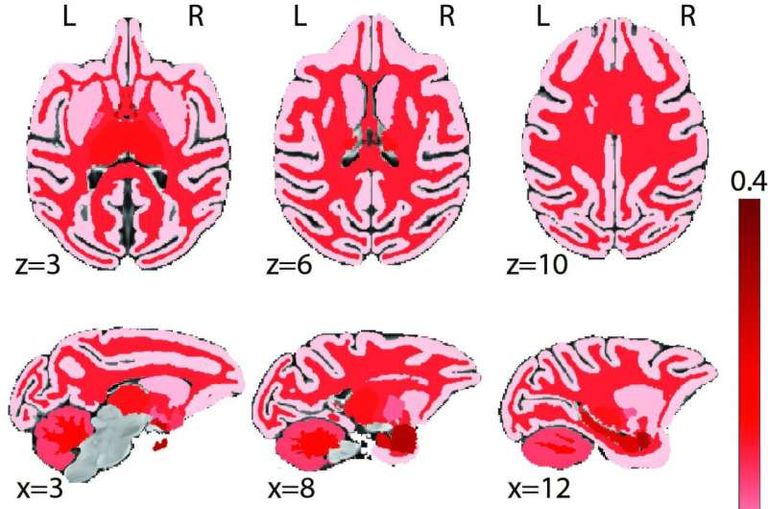

وأظهرت النتائج أن نضوج المادة البيضاء التي تربط الفص الجبهي ببقية مناطق الدماغ كان المؤشر الأقوى على تحسن الأداء العقلي، في حين لعبت التغيرات في سماكة القشرة الدماغية دوراً أقل أهمية.

وقال البروفيسور كريستوس قسطنطينيديس، الباحث الرئيسي في الدراسة: "لطالما ألقى الآباء باللوم على عدم نضج الفص الجبهي في قرارات المراهقين المتهورة، لكن دراستنا تكشف أن التطور الحقيقي يحدث في طريقة تواصل مناطق الدماغ مع بعضها البعض".

وأضاف أن هذه النتائج تسلط الضوء على الدور المحوري للمادة البيضاء في تشكيل التفكير المعقد والذاكرة والانتباه، مشيراً إلى أن الفريق يعتزم توسيع أبحاثه لتشمل مناطق أخرى من الدماغ وفهم كيفية نضوجها عبر مراحل النمو.